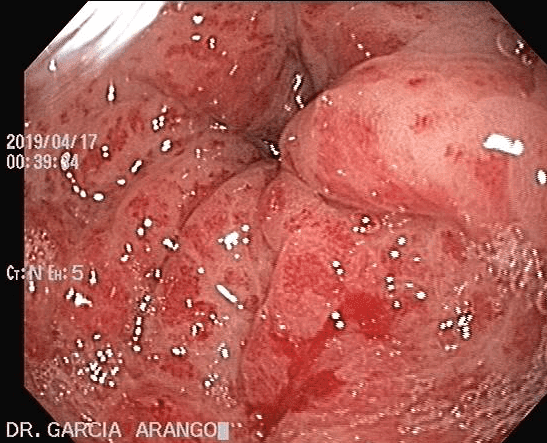

⚕ Endoscopia de alta definición

⚕ Colitis

⚕ Sangrado del tubo digestivo

⚕ Detección de cáncer de tubo digestivo

⚕ Videoendoscopia y biopsias